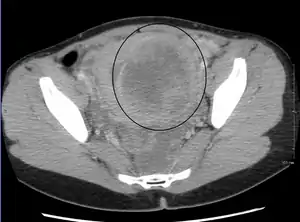

The presence of a uterine fibroid versus an adnexal tumor is made. Fibroids can be mistaken for ovarian neoplasms. An uncommon tumor which may be mistaken for a fibroid is Sarcoma botryoides. It is more common in children and adolescents. Like a fibroid, it can also protrude from the vagina and is distinguished from fibroids.[8] While palpation used in a pelvic examination can typically identify the presence of larger fibroids, gynecologic ultrasonography (ultrasound) has evolved as the standard tool to evaluate the uterus for fibroids. Sonography will depict the fibroids as focal masses with a heterogeneous texture, which usually cause shadowing of the ultrasound beam. The location can be determined and dimensions of the lesion measured. Also, magnetic resonance imaging (MRI) can be used to define the depiction of the size and location of the fibroids within the uterus.

Imaging modalities cannot clearly distinguish between the benign uterine leiomyoma and the malignant uterine leiomyosarcoma, however, the latter is quite rare. Fast growth or unexpected growth, such as enlargement of a lesion after menopause, raise the level of suspicion that the lesion might be a sarcoma. Also, with advanced malignant lesions, there may be evidence of local invasion. A biopsy is rarely performed and if performed, is rarely diagnostic. Should there be an uncertain diagnosis after ultrasounds and MRI imaging, surgery is generally indicated.